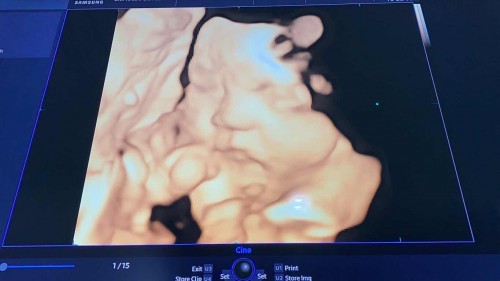

น้ำหนัก 2600kg

แม่ๆทีมกันยาน้ำหนักลูกเท่าไหร่แล้วคะ บ้านนี้ 2600 kg 33 w 3 d คงได้ย้ายมาอยู่ทีมสิงหาแล้ว 😍😍

เหมือนกันเลยค่ะ 33w ลูกน้ำหนัก2600 หมอบอกตัวใหญ่เกิน นัดครั้งหน้าหมอจะดูแล้วน่าจะหาวันนัดผ่า